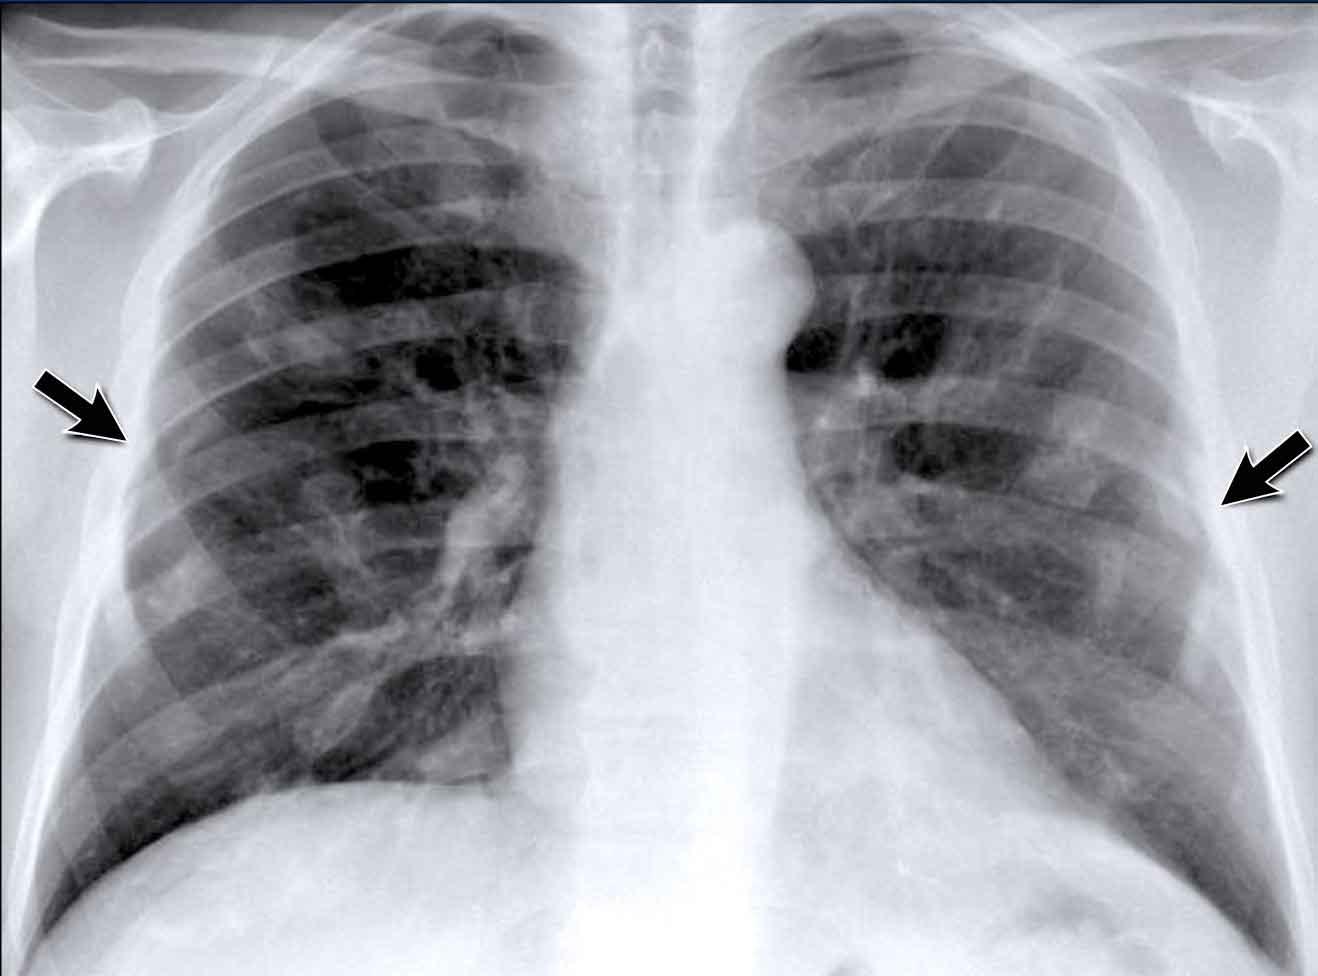

Ví dụ Lâm sàng: Dấu hiệu Kín đáo của Suy tim Sung huyết

Hãy bắt đầu bằng cách xem xét các phim X-quang ngực hiện tại.

Chỉ dựa trên các hình ảnh này, người đọc có thể nghi ngờ suy tim sung huyết (CHF), mặc dù các dấu hiệu còn khá kín đáo.

Bây giờ hãy xem lại phim cũ trước đó…

Việc cuộn qua lại giữa phim hiện tại và phim cũ giúp tăng đáng kể độ tin cậy trong chẩn đoán suy tim sung huyết.

Các dấu hiệu so sánh chính bao gồm:

- Kích thước tim: Tăng nhẹ so với phim trước; tuy nhiên, tim to đã hiện diện từ trước.

- Hệ mạch máu phổi: Cương tụ mạch máu nhẹ gợi ý tăng áp lực tĩnh mạch phổi.

- Hình ảnh mô kẽ: Dấu hiệu kín đáo của phù mô kẽ.

- Tràn dịch màng phổi: Tràn dịch lượng ít hai bên, với thay đổi kín đáo ở bờ dưới-sau của các thùy dưới, gợi ý tích tụ dịch.